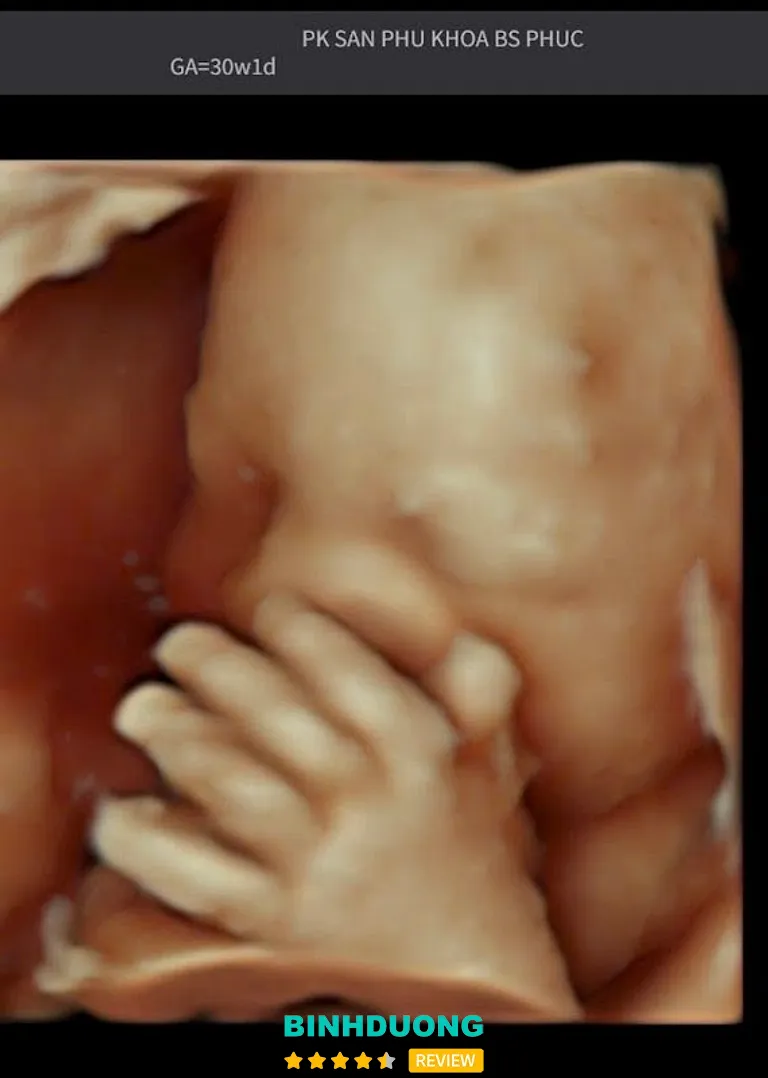

Phòng khám được quảng bá có trang thiết bị hỗ trợ như siêu âm thai — giúp theo dõi sự phát triển của thai nhi, sàng lọc dị tật nếu cần thiết, hỗ trợ kiểm tra sức khỏe phụ khoa.

Dịch vụ tại phòng khám khá toàn diện: khám thai, siêu âm, khám phụ khoa, sàng lọc — phù hợp cho cả thai phụ lẫn phụ nữ muốn kiểm tra sức khỏe sinh sản.